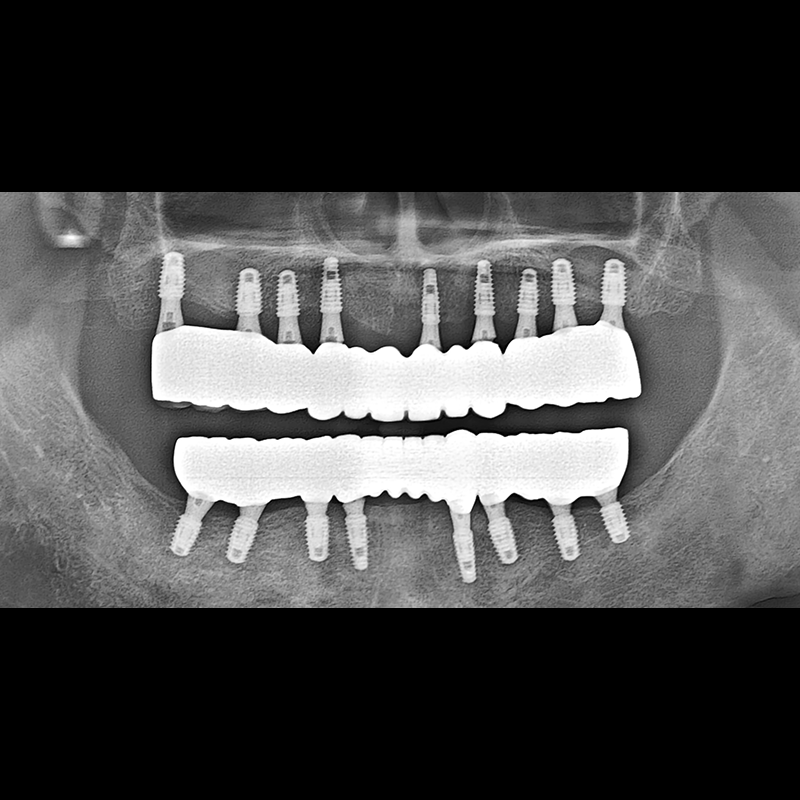

BEFORE AFTER

种植牙前后的照片 2025.05.30

在缺失的牙齿部分和难以挽救的牙齿位置植入了种植牙。